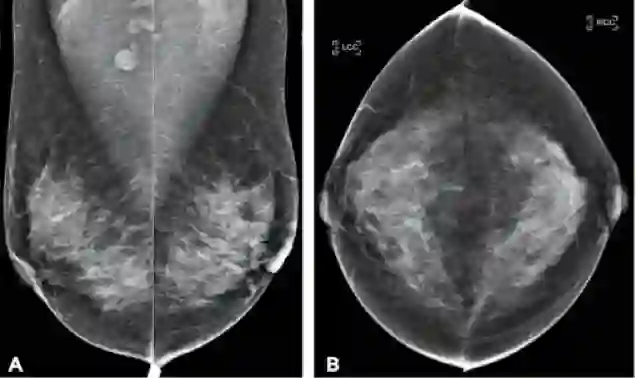

图二 筛查乳房X线照相的例子。这是一个病人的从不同角度拍摄的四张照片。她有一个肿瘤,但是它不是A顶部的圆形位置,它在左乳房中的灰色部分,看起来就像其余的灰色部分。通过观察乳房X线照是很难发现这种细微的差距